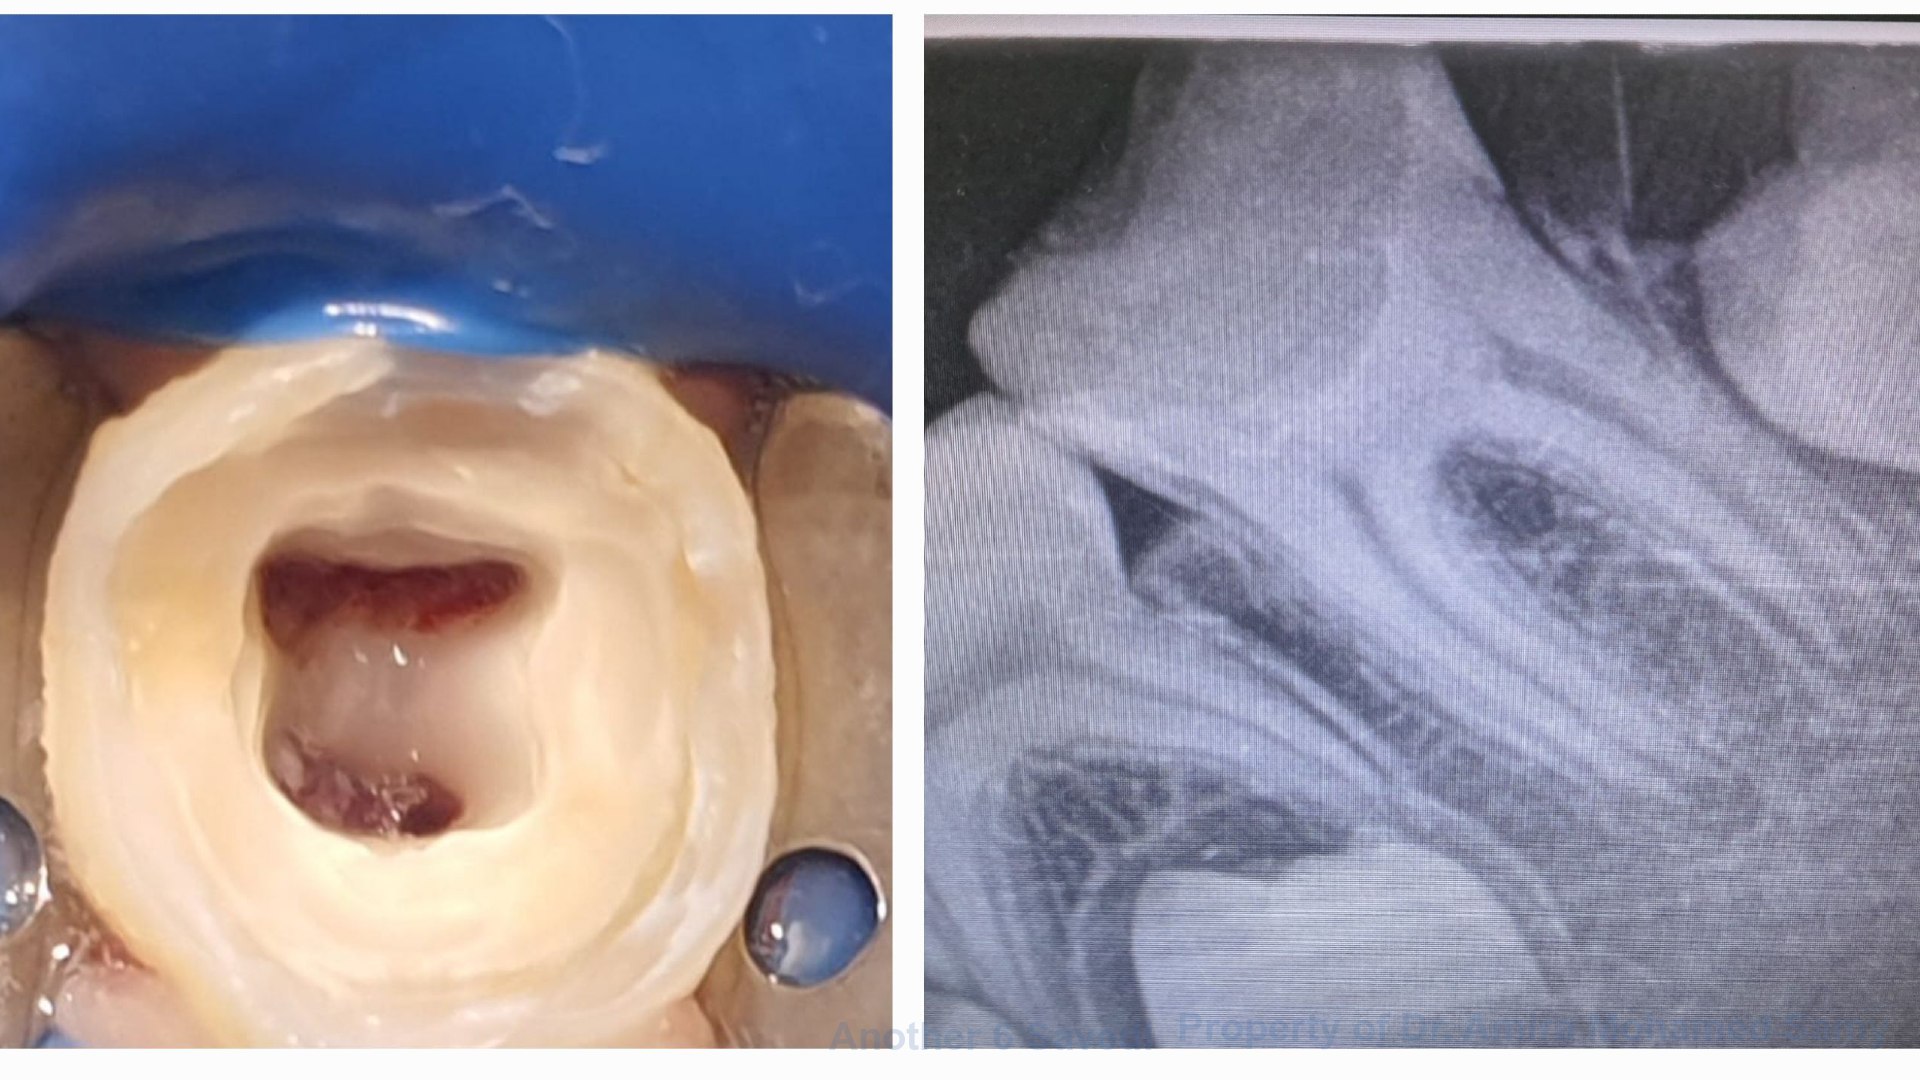

Pre-Operative: Salama is an 8-year-old child that presented to our pediatric dentistry department complaining of pain related to lower left side.

Intra-Operative: Upon clinical examination, a decayed lower left 6 was observed, with no pain on percussion. Radiographic examination showed an open apex maximising our need to perform VPT if possible. Isolation was obtained using rubber dam, complete caries removal was performed, access cavity was completed, and bleeding successfully controlled!

Post-Operative: Voila! MTA pulpotomy is done ✅️